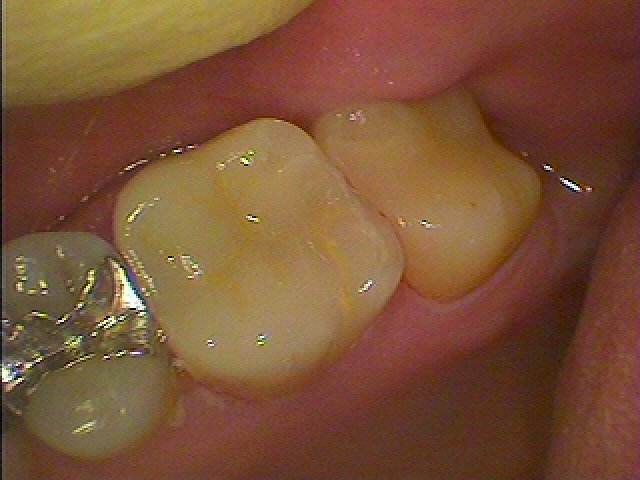

左下7番

白い樹脂の被せが入っていました

記憶にないくらい昔に治療したとのこと

2次カリエスになっています

磨きにくいのが原因かと